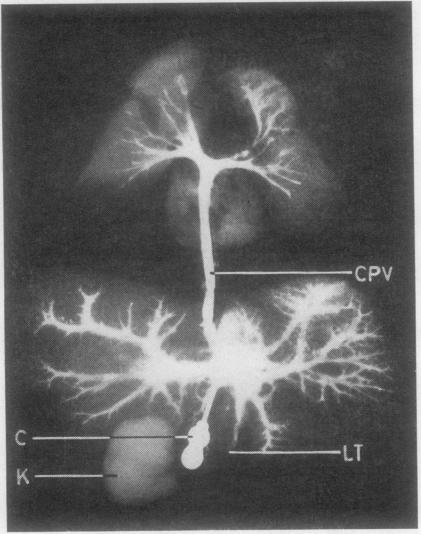

CO-EXISTENT TOTAL ANOMALOUS PULMONARY VENOUS DRAINAGE INTO PORTAL VEIN, DRAINAGE OF LEFT-SIDED INFERIOR VENA CAVA INTO LEFT ATRIUM, AND SPLENIC AGENESIS.